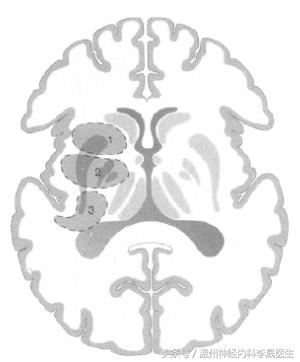

2)壳核出血

①豆纹动脉外侧支破裂,占50~60%

②突发“ 二/三偏”征: 可伴向病灶侧凝视(双眼凝视病灶侧) 优势半球损害有失语;

③出血量大:有意识障碍,可破入脑室;

出血量小:可呈纯运动性/纯感觉性障碍,无头痛、呕吐等,与腔梗不易区分。

壳核出血(A)小壳核范围内的出血,(B)侵犯了内囊,(C)血肿压迫侧脑室

轴位脑切面示意图,(1)前部型累及壳核前部和内囊前肢;(2)中间型包括内囊膝,苍白球和壳核的中间部分(3)后部型累及内囊后肢远端且常累及是辐射并向颞叶蔓延